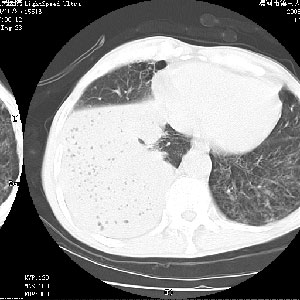

m 老年 发烧、呼吸困难,慢支、肺气肿多年;记的那次是下午大概17:38做的,晚上窒息死亡。

上面的层面就慢性支气管炎肺气肿、肺大泡,别的没有什么、也就不传了。

当时我怀疑:1、阻塞性肺不张早期 2、肺脓肿早期,望老师们发表意见

病灶边缘清---多个含气小腔---近端未见通畅气管影-----支持-----慢性肺脓肿继发阻塞性肺不张

阻塞性肺不张原因-----脓液未排出

3、细支气管肺泡癌可以排除,病变以斜裂为界,呈大片状高密度影,内可见多发小气泡,表明有产气杆菌感染所致,内无明显的支气管“枯树枝征”表现,再结合其临床改变(细支气管肺泡癌临表表现重、影像表现轻)所以不符合细支气管肺泡癌(炎症型)的改变。

病变按肺叶分布,病变内可见多个小空腔影,未见充气支气管影,中间段支气管管腔肺窗示密度欠均匀,下肺支气管分叉处基底段支气管隐约可见,未见明显狭窄,中叶支气管通畅,

考虑:阻塞性肺炎伴小脓肿形成可能性大。(痰栓可能性大)

右下肺实变,内有弥漫分面小气泡而无支气管征,叶间裂前移,呈臌大之形,而无收缩之状,兼纵隔稍左行移,故。不支持不张,倒支持大叶肺叶,如楼上所说,小气泡不象残留之肺,不可以考虑产气菌感染吗。

阻塞性肺炎,肺脓肿形成。依据,右下支气管不通,大片实变形内可见小气泡。不支持肺不张。